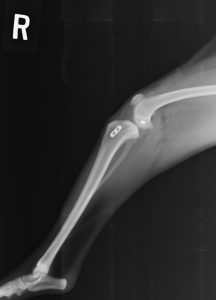

レントゲン検査

膝関節の評価を行います。残念ながら、前十字靭帯はレントゲンに映らないため、靭帯損傷による炎症の存在を調べることになります。そのため、損傷後直後での診断に有用です。

36kg ラブラドール

TPLO

アメリカで研究・開発されたシステムです。脛骨を特殊な器具で半円形に骨きりし、角度を変えることで前十字靭帯を必要としない関節角度を形成・維持します。専用のTPLOプレートを使用します。